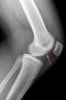

영상 검사

X-ray에서는 간혹 segond fracture나 deep sulcus sign이 보이는 경우 진단에 추가적인 도움을 줄수 있으나 빈도가 흔하지 않거나 발견하기가 쉽지 않습니다.

X-ray : Deep sulcus sign